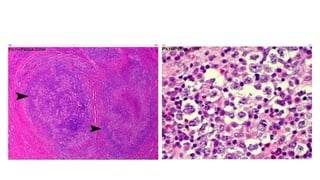

Type III: Bệnh Hodgkin thể hỗn hợp tế bào

- Ðây là típ hay gặp sau thể

xơ nốt (15-30%).

- Nam giới mắc bệnh nhiều

hơn nữ giới và gặp trong mọi

giai đoạn lâm sàng của bệnh

Hodgkin, gần 50% ở giai

đoạn lâm sàng III, IV.

- Thời gian sống thêm của

bệnh nhân tương đối ngắn.

Tiên lượng xấu hơn típ I và

típ II.

• Hạch lympho có sự xâm

nhập đa hình thái, bao gồm

lympho bào, mô bào, tương

bào, bạch cầu đa nhân ưa

toan và trung tính.

• Nhiều tế bào Reed-Sternberg

điển hình và các tế bào

Hodgkin đơn nhân.

• Thường thấy các ổ hoại tử và

xơ hóa. Tất cả tạo nên hình

ảnh hỗn hợp tế bào.

Bệnh Hodgkin thể hỗn hợp tế bào

• #34 Hình 1: Tế bào Reed-Sternberg Là những tế bào ác tính đặc trưng của bệnh Hodgkin, đặc hiệu để chẩn đoán bệnh Hodgkin. Tế bào Reed-Sternberg điển hình có kích thước lớn 20-50µm hoặc hơn. Bào tương rộng, thuần nhất hoặc dạng hạt, ưa toan nhẹ. Nhân lớn. Kích thước thay đổi, màng nhân dày, chất nhiễm sắc thô vón và tập trung sát màng nhân. Hạt nhân rất to, ưa toan, nằm giữa nhân và tách biệt với chất nhiễm sắc tạo nên một quầng sáng quanh hạt nhân. Ðôi khi thấy tế bào hai nhân đối xứng với nhau tạo nên hình ảnh “soi gương” hay “mắt cú”. Những tế bào lớn, một nhân nhưng nhân không có múi, hạt nhân nổi rõ gọi là tế bào Hodgkin hoặc tế bào dạng Sternberg. Nguồn gốc của tế bào Reed-Sternberg và các biến thể của nó là những nguyên bào lympho phát triển từ các tế bào Th. Hình 2: Tế bào Reed-Sternberg; hình ảnh cho thấy lymphocytes bình thường so với một tế bào Reed-Sternberg, có kích thước lớn, bất thường lymphocytes có thể chứa nhiều hơn một hạt nhân. Những tế bào này được tìm thấy trong u lymphô Hodgkin

• #46  Hạch lympho có sự xâm nhập đa hình thái, bao gồm lympho bào, mô bào, tương bào, bạch cầu đa nhân ưa toan và trung tính. Nhiều tế bào Reed-Sternberg điển hình và các tế bào Hodgkin đơn nhân. Thường thấy các ổ hoại tử và xơ hóa. Tất cả tạo nên hình ảnh hỗn hợp tế bào.

• #47  ReedSternberg tế bào có trong một nền của eosinophils, tế bào plasma, bạch huyết bào, và không điển hình các tế bào đơn hạt nhân. Sợi xơ thường không có.

• #49  1. Một ví dụ khác của u lymphoma MC-Hodgkin có nền viêm hỗn hợp gồm các lympho bào nhỏ, bạch cầu ái toan (mũi tên dài), tế bào biểu mô, và các tế bào RS rải rác (đầu mũi tên). 2. Khám nghiệm nhiều hơn về u lymphô Hodgkin liên kết cho thấy các đặc trưng điển hình bao gồm sự xâm nhập của tế bào viêm kết hợp gồm eosinophils phong phú (mũi tên), tế bào plasma (mũi tên dài), bạch huyết bào nhỏ. Lưu ý một tế bào RS trong số thâm nhập này.